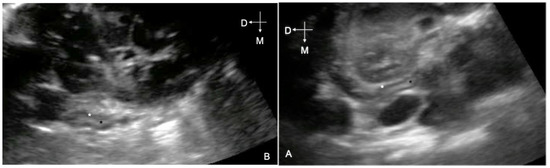

- Beccati, F.; Lauteri, E.; Cercone, M.; Gialletti, R. Ultrasonographic technique and appearance of adrenal gland in neonatal foals: A pilot study. J. Equine Vet. Sci. 2018, 61, 13–17. [Google Scholar] [CrossRef]

- Lauteri, E.; Mariella, J.; Beccati, F.; de Graaf-Roelfsema, E.; Castagnetti, C.; Pepe, M.; Peric, T.; Barbato, O.; Montillo, M.; Rouge, S.; et al. Ultrasonographic measurement of the adrenal gland in neonatal foals: Reliability of the technique and assessment of variation in healthy foals during the first five days of life. Vet. Record. 2020, 187, 1–6. [Google Scholar] [CrossRef] [PubMed]